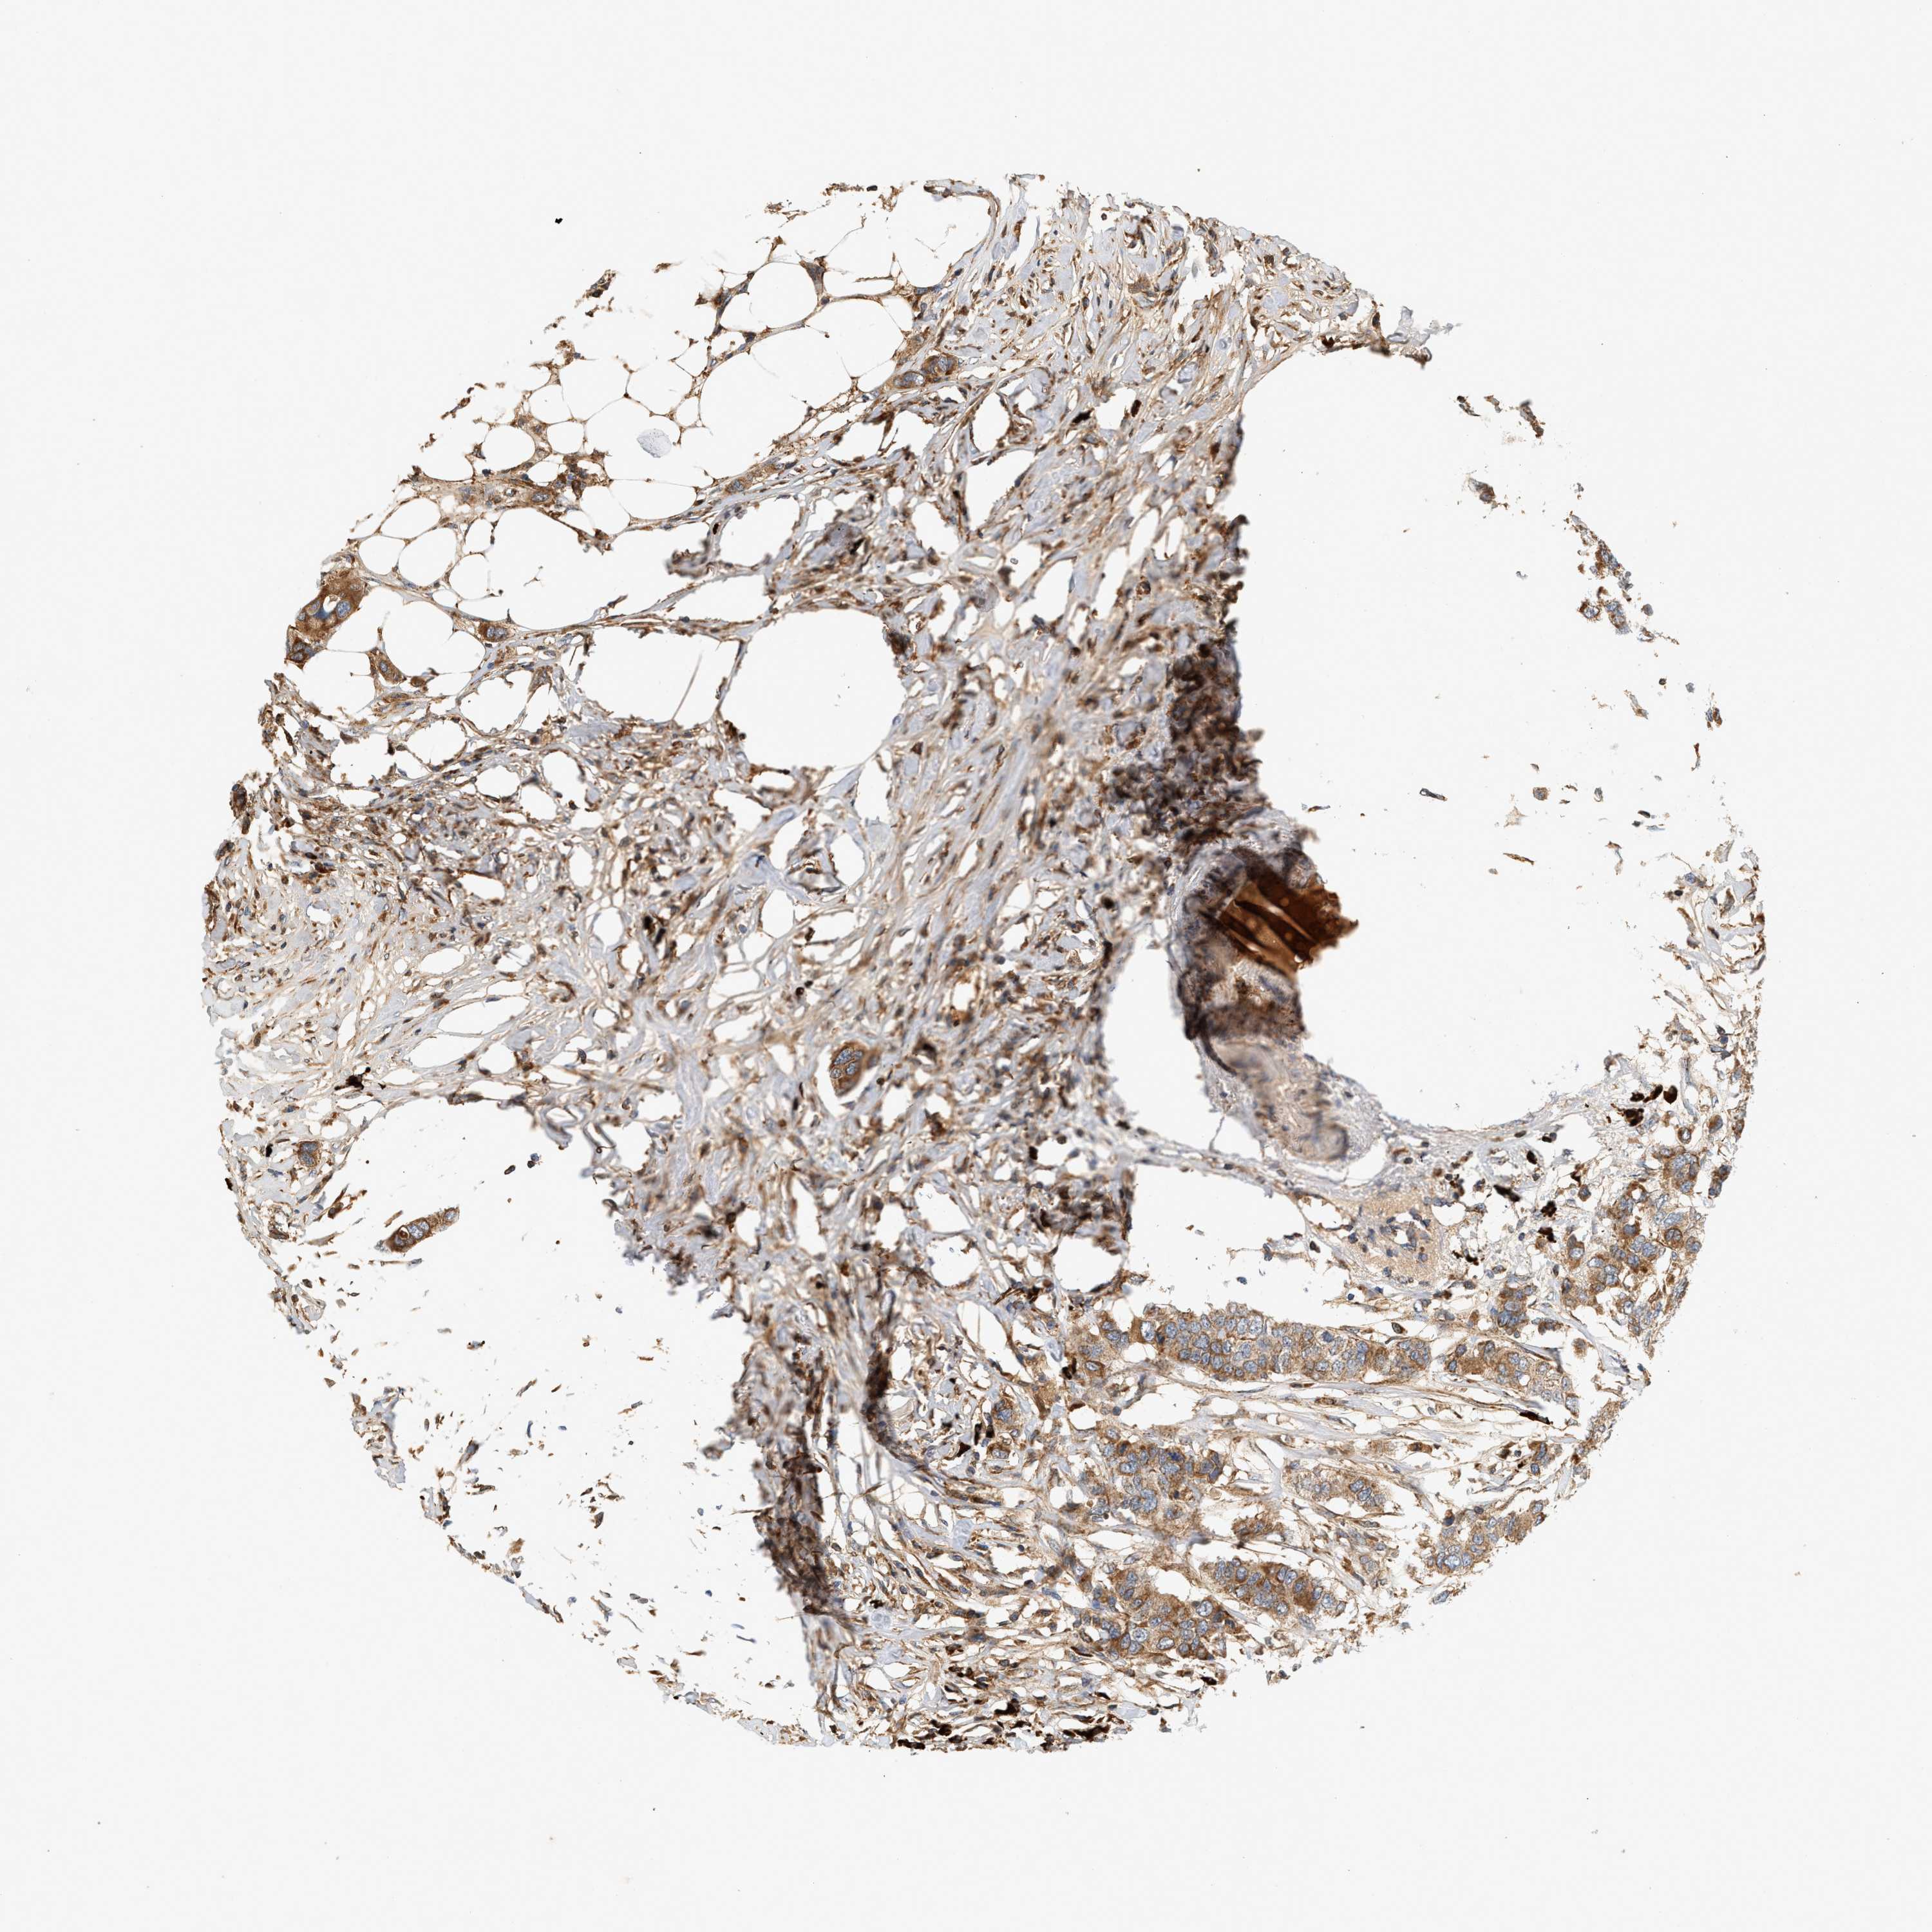

CANCER BREAST CANCER Show tissue menu

BRCA TCGA BRCA VALIDATION PROTEIN EXPRESSION